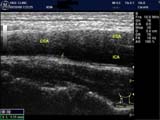

頚動脈エコー装置

頚動脈エコー装置 頚動脈エコー装置

動脈硬化が疑われた際には、やはり直接、確認できる頚動脈エコーが必要と考えます。

私は、必ず患者さんの、動脈の状態を確認して、内服薬の選定を行います。常に、根拠を持って治療していきます。